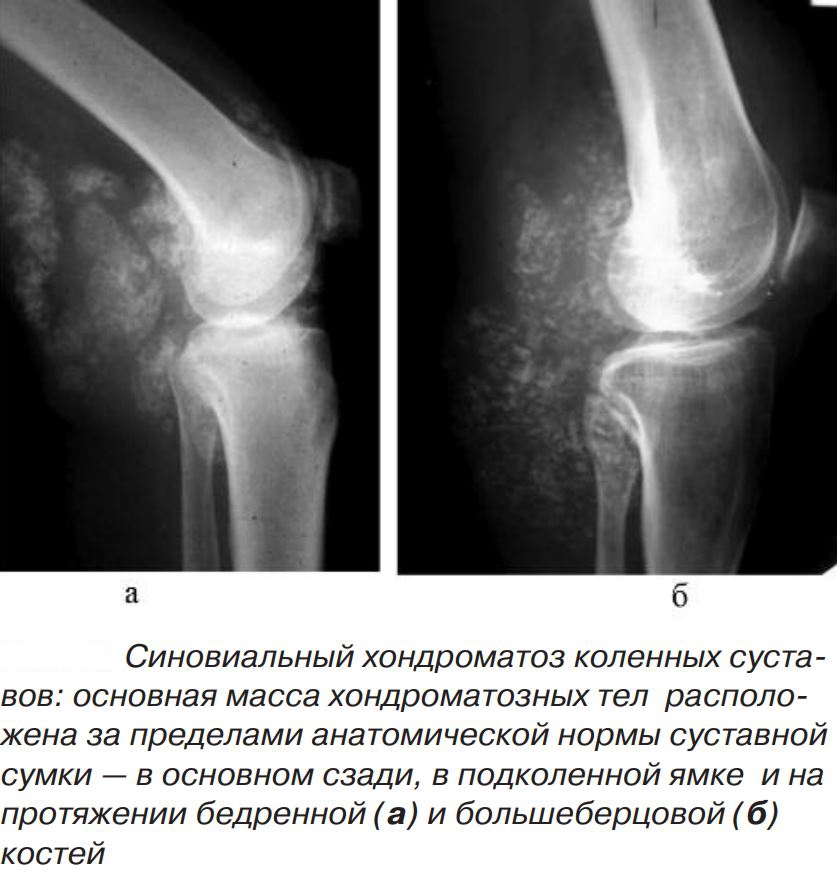

На полученных рентгенографических изображениях хондромные тела визуализируются в виде множественных шаровидных или овальных теней с четкими очертаниями. Но это исследование информативно только при наличии включений с обызвествленными участками.

Синовиальная оболочка состоит из особых клеток, определяющих ее функциональную активность. Но при хондроматозе происходит их замещение хрящевой тканью с образованием плотным узелков. При проведении диагностических исследований они визуализируются в виде единичных или множественных бугорков. Большая часть узелков «встроена» во внутреннюю поверхность суставной сумки, а некоторые возвышаются над ней на ножке. Такие уплотнения со временем отделяются и начинают свободно передвигаться во внутрисуставном пространстве. Они состоят из гиалинового хряща, включающего очаги обызвествления.

Хондромные тельца округлые, прочные, отличаются друг от друга размерами. Обычно их диаметр не превышает несколько миллиметров, но встречаются крупные 4-5-сантиметровые экземпляры. В коленном суставе может одновременно находиться до нескольких сотен свободно перемещающихся внутрисуставных тел. Метаплазия синовиальной оболочки становится причиной ее деструкции: